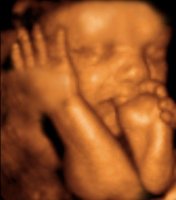

При необходимости вмешательств возможно использование новейших безболезненных методик с использованием лазера и криогенных технологий. Для ультразвуковых исследований применяют новейший ультразвуковой сканер с допплером и 3D | 4D визуализацией GE Healthcare пр-ва 2016 года (США) премиум-класса - это полностью цифровая универсальная цветная ультразвуковая система, построенная с использованием технологии TruScan - эксклюзивной технологии GE, обеспечивающей непревзойденное качество изображения, расширенные возможности обработки данных и высочайший уровень эргономики.

ComfortScan - новый подход к созданию УЗ систем с высочайшим уровнем эргономики для обеспечения максимального комфорта пациента и пользователя, имеет постоянно-волновой допплер, цветовое картирование и функции 3D и 4D визуализации, с возможностью автоматического трехмерного сканирования в режиме реального времени с использованием специализированных датчиков, а также дуплексные и триплексные исследования. Благодаря множеству инноваций и инженерных решений, применённых в данной системе появилась возможность высокоточных, безвредных ультразвуковых исследований Premium-класса как при уточнении диагноза, так и при скринингах беременных на любом сроке с возможностью оценки кровотока, допплерографии, цервикометрии, 3D и 4D визуализации с возможностью первой записи Вашего малыша на диск или другой носитель.